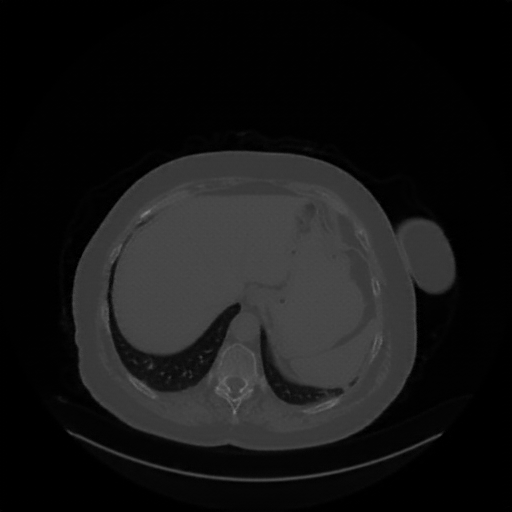

Original NATIVE CT scan (input)

Lung window (WL -600, WW 1500 β†’ Low βˆ’1350, High +150)

Reconstructed NATIVE CT scan (cycle consistency)

Original VENOUS CT scan

Mediastinum window (WL 40, WW 400 β†’ Low βˆ’160, High +240)

Generated VENOUS CT scan (A→B translation)